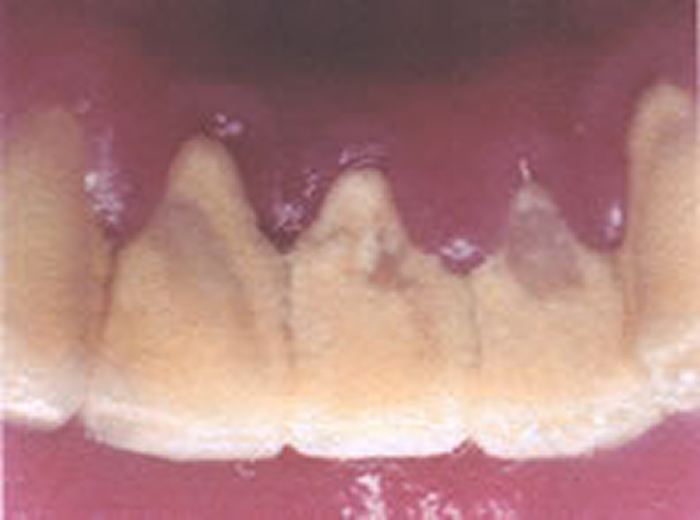

歯肉炎~軽度の歯周炎歯周病原菌

歯と歯ぐきの間にプラークがたまって歯ぐきが腫れ、出血しやすくなっています。

歯を支える骨にはまだあまり影響がありません。